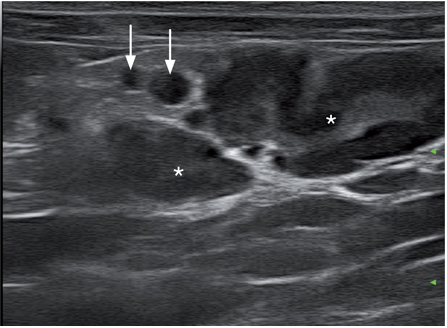

淋巴结病与反应性淋巴结病,炎症和肿瘤有关(图16)。超声上不能完全区分正常淋巴结,反应性淋巴结,以及恶性转移性淋巴结,他们之间有相似之处(图17)。形态较大,回声混杂的淋巴结可能为良性或恶性肿瘤浸润的淋巴结,也可与脓性肉芽肿(图18)或肿瘤(图19)相关。应该细针抽吸淋巴结做细胞学诊断。

肉芽肿和脓性肉芽肿不是很常见。它们不属于腹腔内任何一个器官,是均一的高回声团块。猫FIP的肠系膜肉芽肿块可呈现多种形态(图20.视频1)。FIP的猫在肝脏上会有弥散性或局灶性高回声结节,肾脏上会有髓质缘征,肾周低回声带,腹膜和后腹膜问隙积液,腹部淋巴结呈低回声团块,脾脏低回声以及睾丸炎。